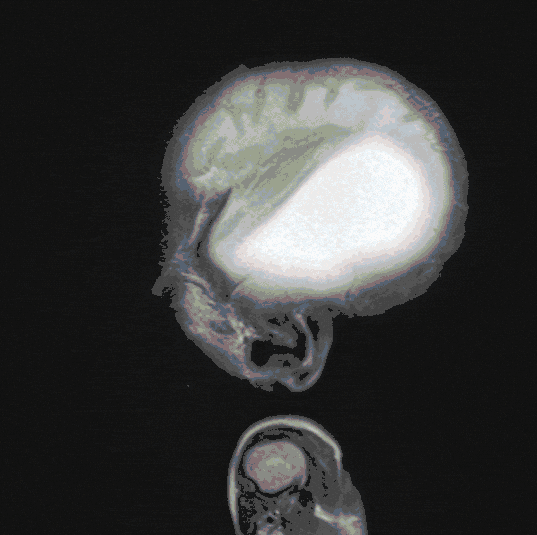

Hydrocephalus

Hydrocephalus (water on the brain) is the result of a drainage or resorption disorder of the cerebrospinal fluid. A variety of diseases can lead to hydrocephalus for a wide range of reasons. Cerebral pressure symptoms are the result with sometimes severe, acute and threatening disease states and must be treated in the long term.